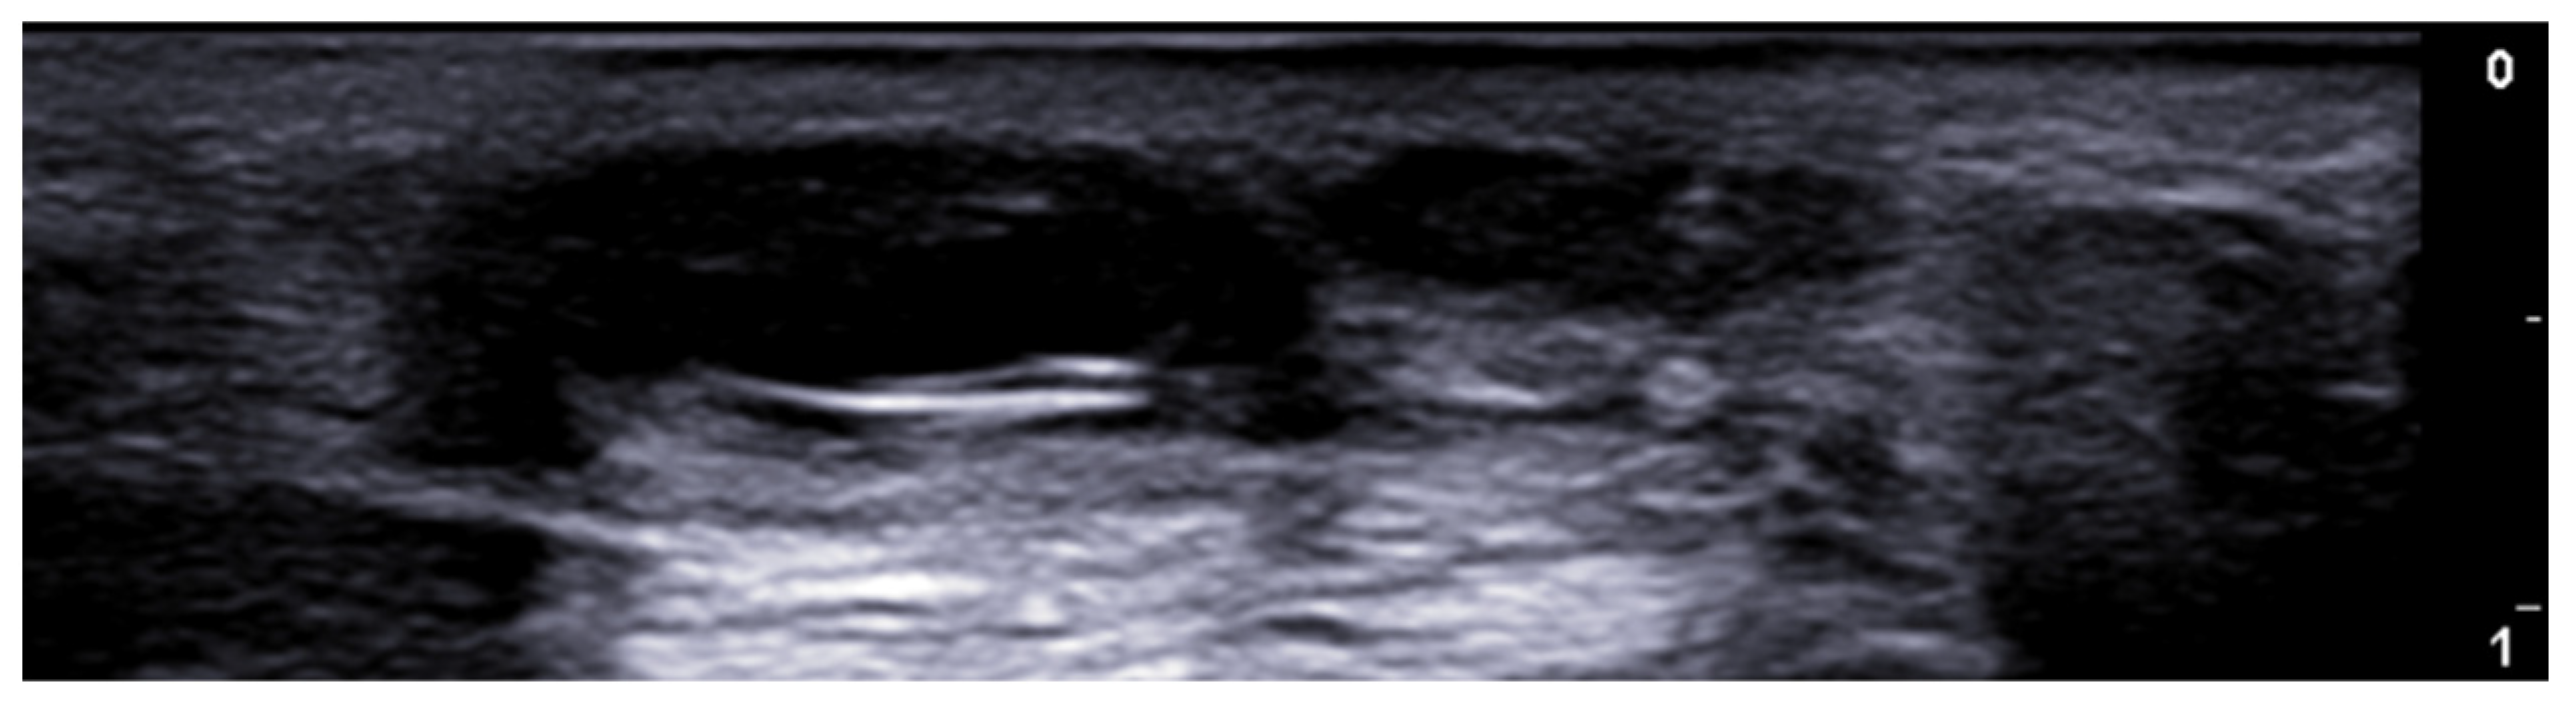

- Del Vecchio, D.; Kenkel, J.M. Practice Advisory on Gluteal Fat Grafting. Aesthetic Surg. J. 2022, 42, 1019–1029. [Google Scholar] [CrossRef]

- Vidal-Laureano, N.; Huerta, C.T.; Perez, E.A.; Earle, S.A. Augmented Safety Profile of Ultrasound-Guided Gluteal Fat Transfer: Retrospective Study with 1815 Patients. Aesthetic Surg. J. 2024, 44, NP263–NP270. [Google Scholar] [CrossRef] [PubMed]

- Elsaftawy, A.; Ostrowski, P.; Bonczar, M.; Stolarski, M.; Gabryszuk, K.; Bonczar, T. Buttock Augmentation with Ultrasonic Liposuction and Ultrasound-Guided Fat Grafting: A Retrospective Analysis Based on 185 Patients. J. Clin. Med. 2024, 13, 1526. [Google Scholar] [CrossRef]

- Elsaftawy, A.; Ostrowski, P.; Bonczar, M.; Stolarski, M.; Gabryszuk, K.; Bonczar, T. Enhancing Buttock Contours: A Safer Approach to Gluteal Augmentation with Ultrasonic Liposuction, Submuscular Implants, and Ultrasound-Guided Fat Grafting. J. Clin. Med. 2024, 13, 2856. [Google Scholar] [CrossRef]

- Wang, B.; He, P.; Zhao, R. B-ultrasound-assisted gluteal fat grafting in Asians: A prospective study of quantitative results from three-dimensional imaging and B-ultrasound analysis. J. Plast. Reconstr. Aesthetic Surg. 2024, 94, 12–19. [Google Scholar] [CrossRef] [PubMed]